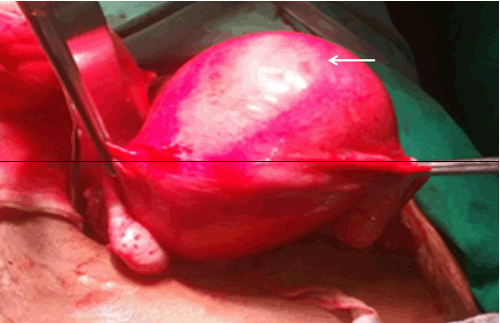

With a provisional diagnosis of fibroid uterus (myoma) with intermittent retention of urine and heavy menstrual bleeding, the patient underwent total abdominal hysterectomy with bilateral salpingo-oophorectomy (Figure 3) under regional anesthesia. On gross examination, the uterus with cervix and bilateral appendages measured 13x16x8 cm (Figure 4). Cut section showed a large intramural fibroid in the fundus and body of uterus measuring 8.5x6 cm, which was greyish white, firm, solid with whorling.

Figure 3: Intra-operative picture showing the large myoma (arrow) bulging anteriorly.